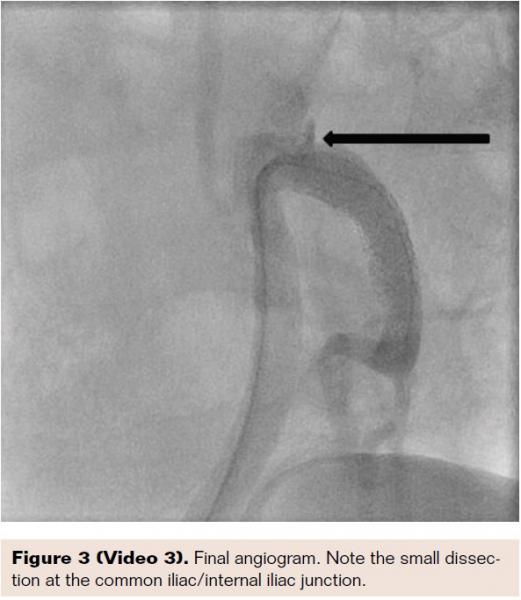

A 78-year-old active physician presented with right thigh and buttock claudication and impotence. Prescription erectile dysfunction (ED) medications were ineffective for the impotence. He was evaluated by primary care and found to have a normal testosterone level. The patient was a previous smoker, and also had hyperlipidemia and had a left anterior descending stent placed 13 years prior to this visit. He underwent right groin abdominal and long leg run-off. In addition to bilateral anterior tibial 100% occlusion, he had a subtotal proximal internal iliac artery complex 90% stenosis. Measurement of the gradient revealed a 60 mm drop across the lesion. A 6 Fr Destination sheath (Terumo Corporation) was placed and the lesion was crossed with a Cougar wire (Medtronic). We predilated the stenosis with a 5 x 20 mm Armada balloon (Abbott Vascular). We then placed a 7 x 19 mm Omnilink stent (Abbott Vascular). Unfortunately, in spite of the predilation, the stent didn’t fully cover the complex stenosis; this may have been due to the “watermelon seeding” effect. We therefore placed an 8 x 29 mm Omnilink stent, which resolved the stenosis. The gradient was reduced to zero.

Six months after the procedure, the patient reported that he was achieving full erections and was able to have intercourse with completion. Incidentally, he was happy to report that his right thigh and buttock claudication had resolved. It is unusual that there was no common iliac artery disease in this patient, as the isolated internal iliac artery stenosis would in itself not be a likely cause of buttock claudication. His left internal iliac system was free of disease. Many of us have had extensive experience in either trying to maintain internal iliac arteries with endovascular aneurym repair, or in some cases jailing them with common and external iliac intervention. I do believe this can result in not only impotence, but painful hip claudication. An increased awareness of this circulation for males needs to be emphasized. From a technical standpoint, we can approach these vessels from the radial approach in shorter male patients, but in general a contralateral approach is easier. In this case, we were able to complete a successful procedure even though we were in a less ideal ipsilateral position. Since these patients are at risk for continued peripheral vascular disease progression, as well as coronary artery disease, continued vigilance will be necessary in these patients. Antiplatelet agents and lipid-lowering agents are essential in many of these individuals.